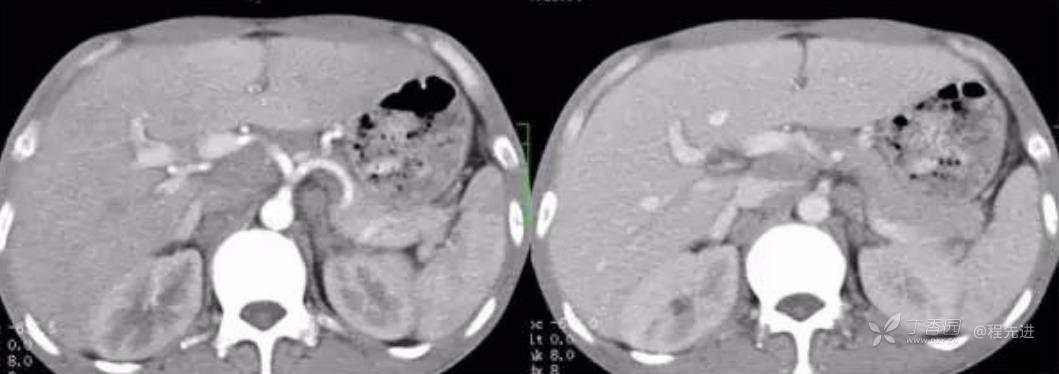

左动脉期,右静脉期

动脉期CT值32HU,静脉期CT值54HU